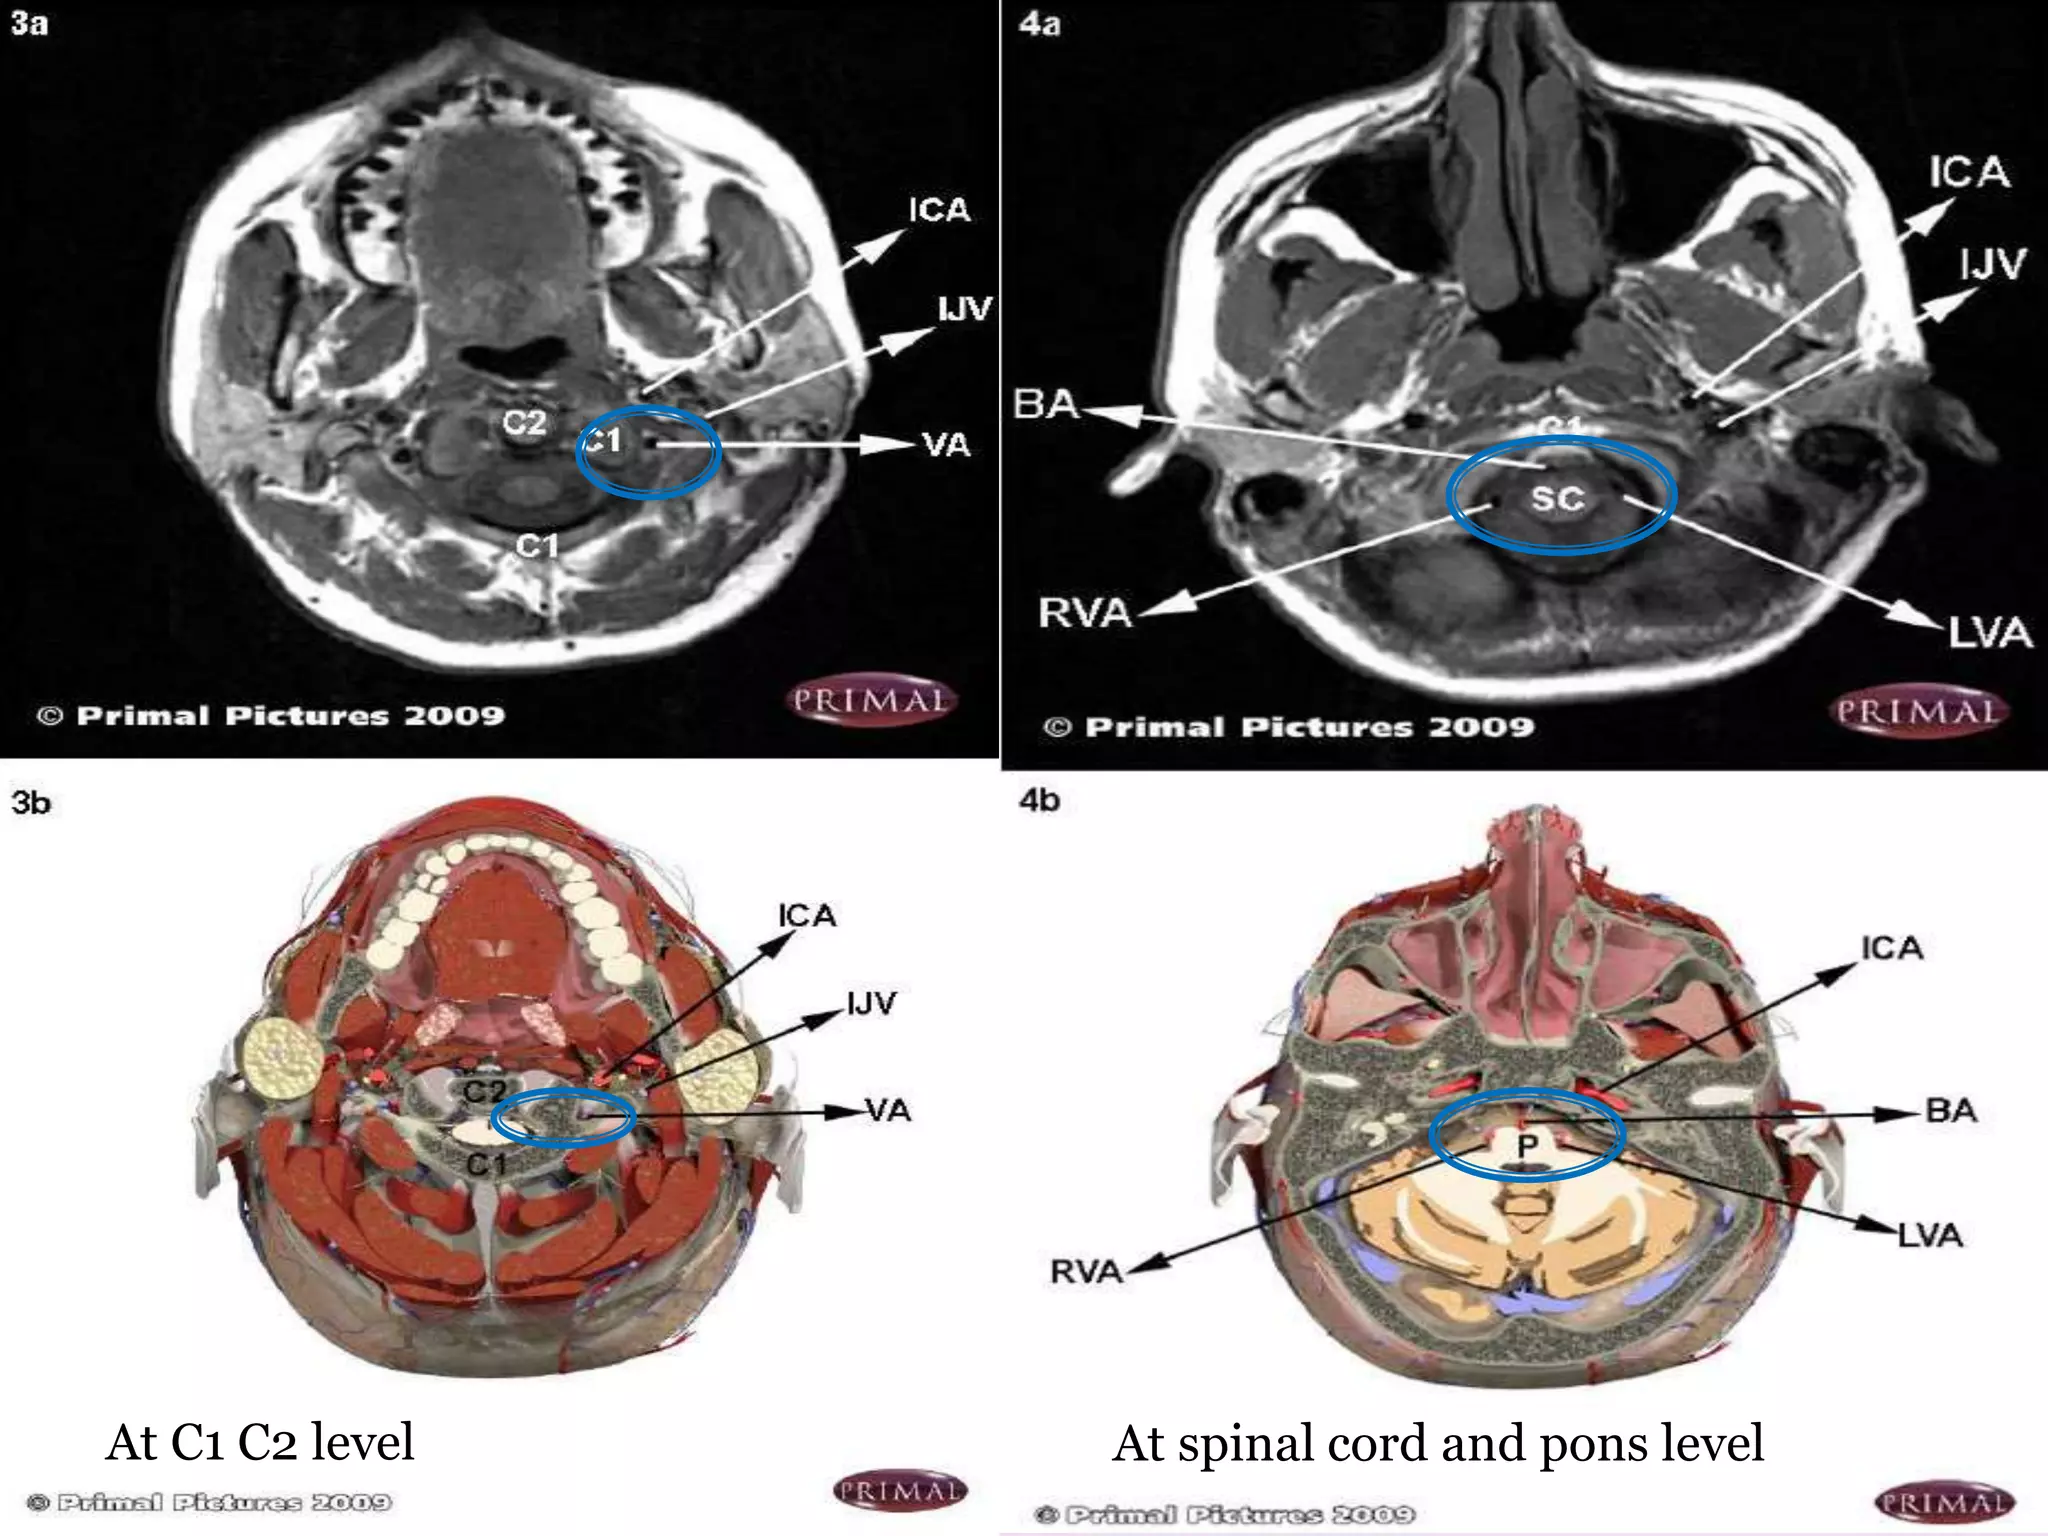

V1 Courses –Cephalad to enter

transverse foramina at C6

Ascend directly to C2 (V2)

Turns laterally and superiorly

thro C1 vertebral foramina

Looping posteriorly along atlas

V3 extraspinal

Each VA passes superomedially

thro foramen magnum

In Posterior fossa

anterior to medulla (intradural )

VAs unite to form basilar artery

From subclavian arteries

Left VA dominant 50%

At C1 C2 level At spinal cord and pons level

V1 Courses –Cephaladto enter transverse foramina at C6 Ascend directly to C2 (V2) Turns laterally and superiorly thro C1 vertebral foramina Looping posteriorly along atlas V3 extraspinal Each VA passes superomedially thro foramen magnum In Posterior fossa anterior to medulla (intradural ) VAs unite to form basilar artery From subclavian arteries Left VA dominant 50%

At C1 C2level At spinal cord and pons level